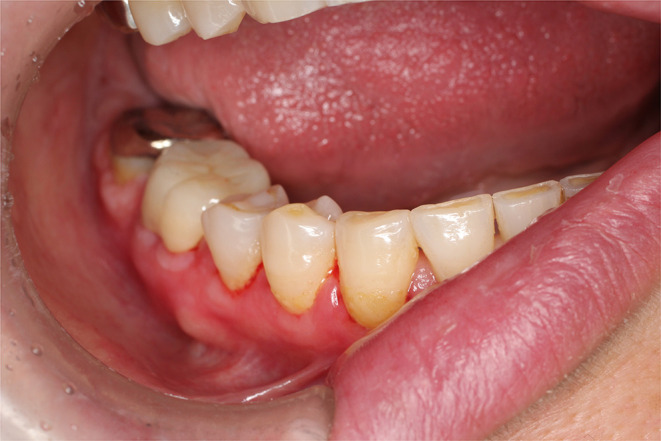

Patients and methods: A 55-year-old female presented with redness and pain near the buccal gingiva of the right mandibular first molar, along with white lace-like patches. Intraoral examination revealed multiple metal restorations, and element analysis identified Zn and Co in several crowns. Based on these findings, a metal allergy was diagnosed. All metal crowns were replaced with zirconia. However, symptoms persisted. A biopsy later confirmed OLP, and steroid therapy was initiated.